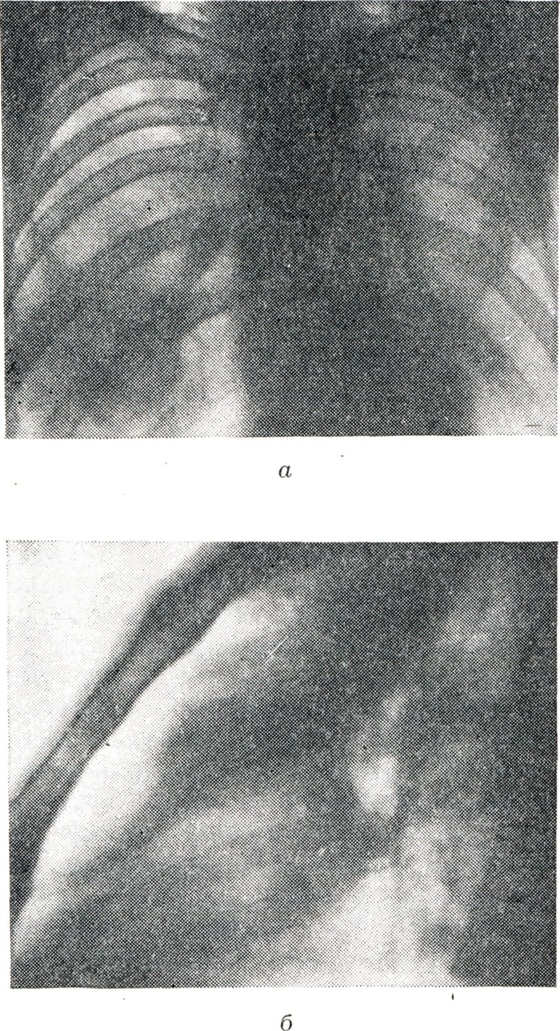

Рис. 3.

Рентгенологическая картина тотальных и долевых ателектазов обоих легких (на схеме изображены черным цветом): 1 — ателектаз всего правого легкого; 2 — ателектаз всего левого легкого; 3—12 — ателектаз отдельных долей правого и левого легких. Правое легкое: ателектаз верхней доли (3 и 4); ателектаз средней доли (5 и 6); ателектаз нижней доли при небольшом (7) и значительном (8) ее спадении. Левое легкое: ателектаз верхней доли при небольшом (9) и значительном (10) ее спадении; ателектаз нижней доли при небольшом (11) и значительном (12) ее спадении, (а — прямая проекция, б — боковая проекция.)

Рис. 4.

Рентгенологическая картина сегментарных ателектазов (на схеме изображены черным цветом): 1 — верхушечного сегмента; 2 — заднего сегмента; 1 + 2 —верхушечно-заднего слева; 3 — переднего; 4 — наружного справа, верхнего язычкового слева; 5 — внутреннего справа, нижнего язычкового слева; 6 — верхнего нижней доли; 7 — нижне-внутреннего; 8 — нижне-переднего; 9 — нижне-наружного; 10 — нижне-заднего. (а — прямая проекция, б — боковая проекция.)

Рис. 4 продолжение.